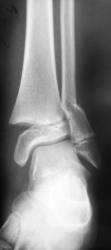

Направлен пациент хирургом для рентгенографии голеностопного сустава.

Что посоветуете уважаемые коллеги?

Согласен с Вами, коллега, без эндопротезирования здесь не обойтись.

Эээ... Простите. Без эндопротезирования голеностопного сустава? По поводу последнего случая?

По всей видимости, это по поводу тазобедренных суставов.